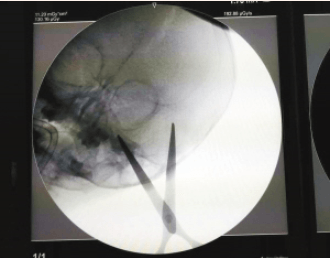

急救绿色通道打开,桐桐被迅速送进手术室,医护人员立即到位。检查结果显示:剪刀的两个刀片,一个刀片刺入桐桐眼附近,距离眼底不到1厘米,另一个刀片从太阳穴附近刺入,距离颞浅动脉不到1厘米。

手术从上午10点50分开始,持续到11点40分,剪刀被顺利取出。张杰说,孩子还需要再监护一两天,一切顺利的话,可以在一周之后出院,应该不会留下什么后遗症。